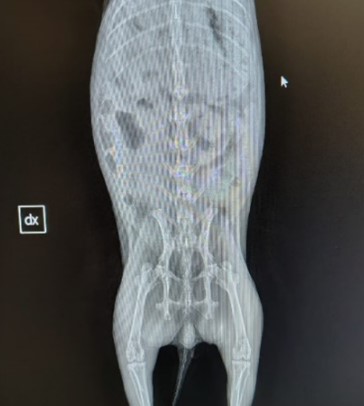

Eseguito esame radiografico in proiezione VD che non rileva lesioni a carico del rachide e degli arti posteriori.